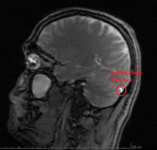

Weil ich Angst habe das mein Hirn von Schwermetalle geschädigt ist, und die Radiologie es nicht sieht ( weil die Microweiße Punkte im Hirn keiner Bedeutung zuweisen, diese sich aber über kurz oder Lang vergrößern können) habe ich die CD's der beiden MRT's aus den letzten beiden Jahren angefordert und möchte mittels Daunderers Bildmaterial mein Hirn mal vergleichen. Vielleicht erkenne ich ja Auffälligkeiten.